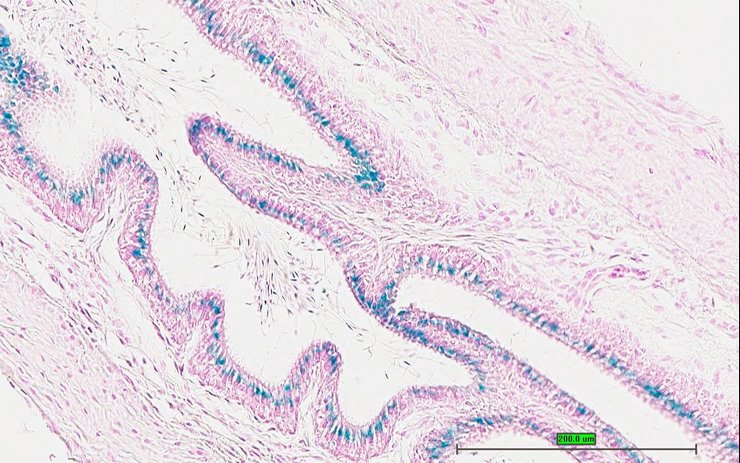

TS28: ductus deferens Present UC Davis_1870412 vas deferens